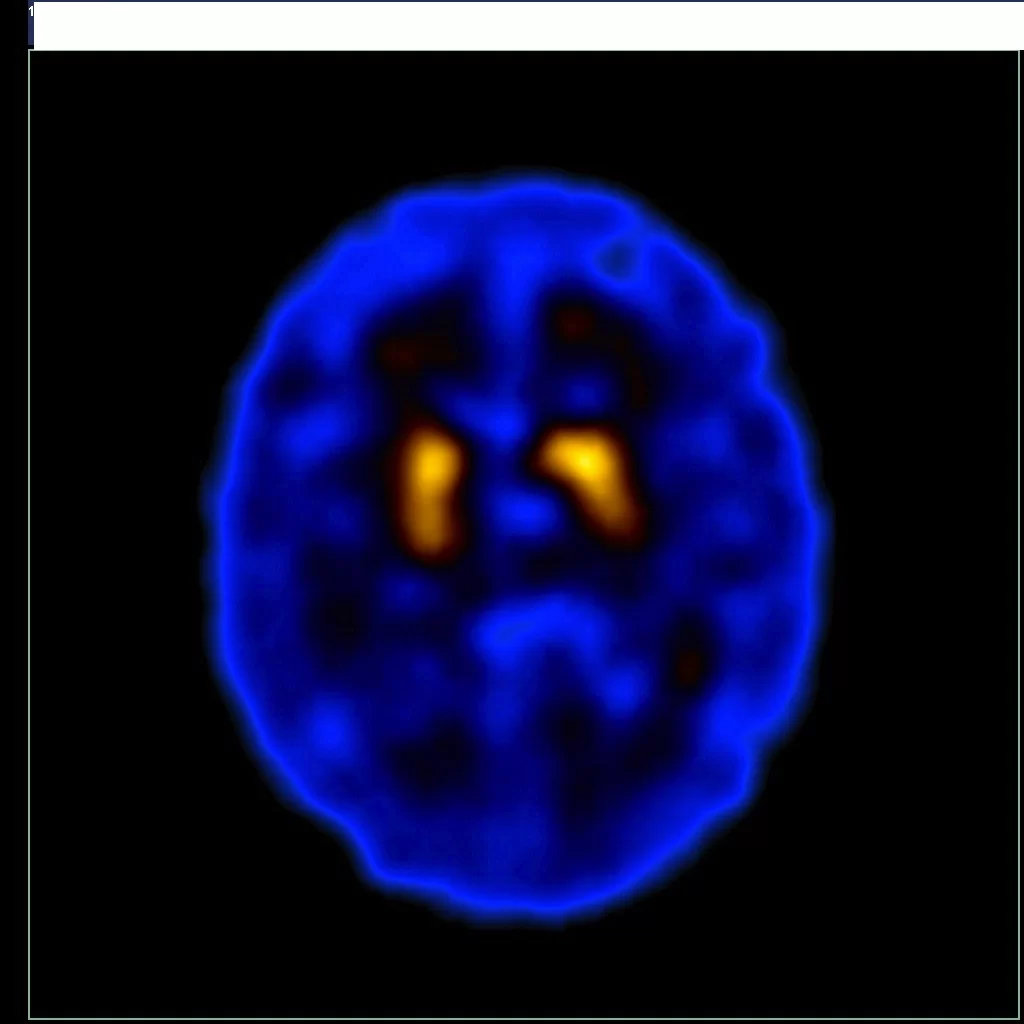

Cintilografia Cerebral com Trodat e Cintilografia de Perfusão Cerebral:

- Cintilografia Cerebral com Trodat: Avalia a função cerebral e pode ajudar a diagnosticar doenças neurológicas como a doença de Parkinson.

- Cintilografia de Perfusão Cerebral: Mede o fluxo sanguíneo no cérebro e é crucial para identificar áreas de diminuição do fluxo associadas a doenças neurológicas.